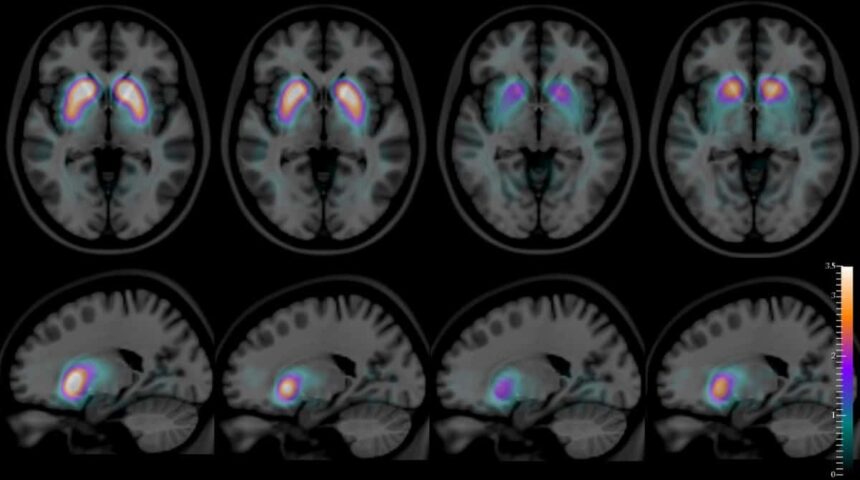

- MRT des Gehirns